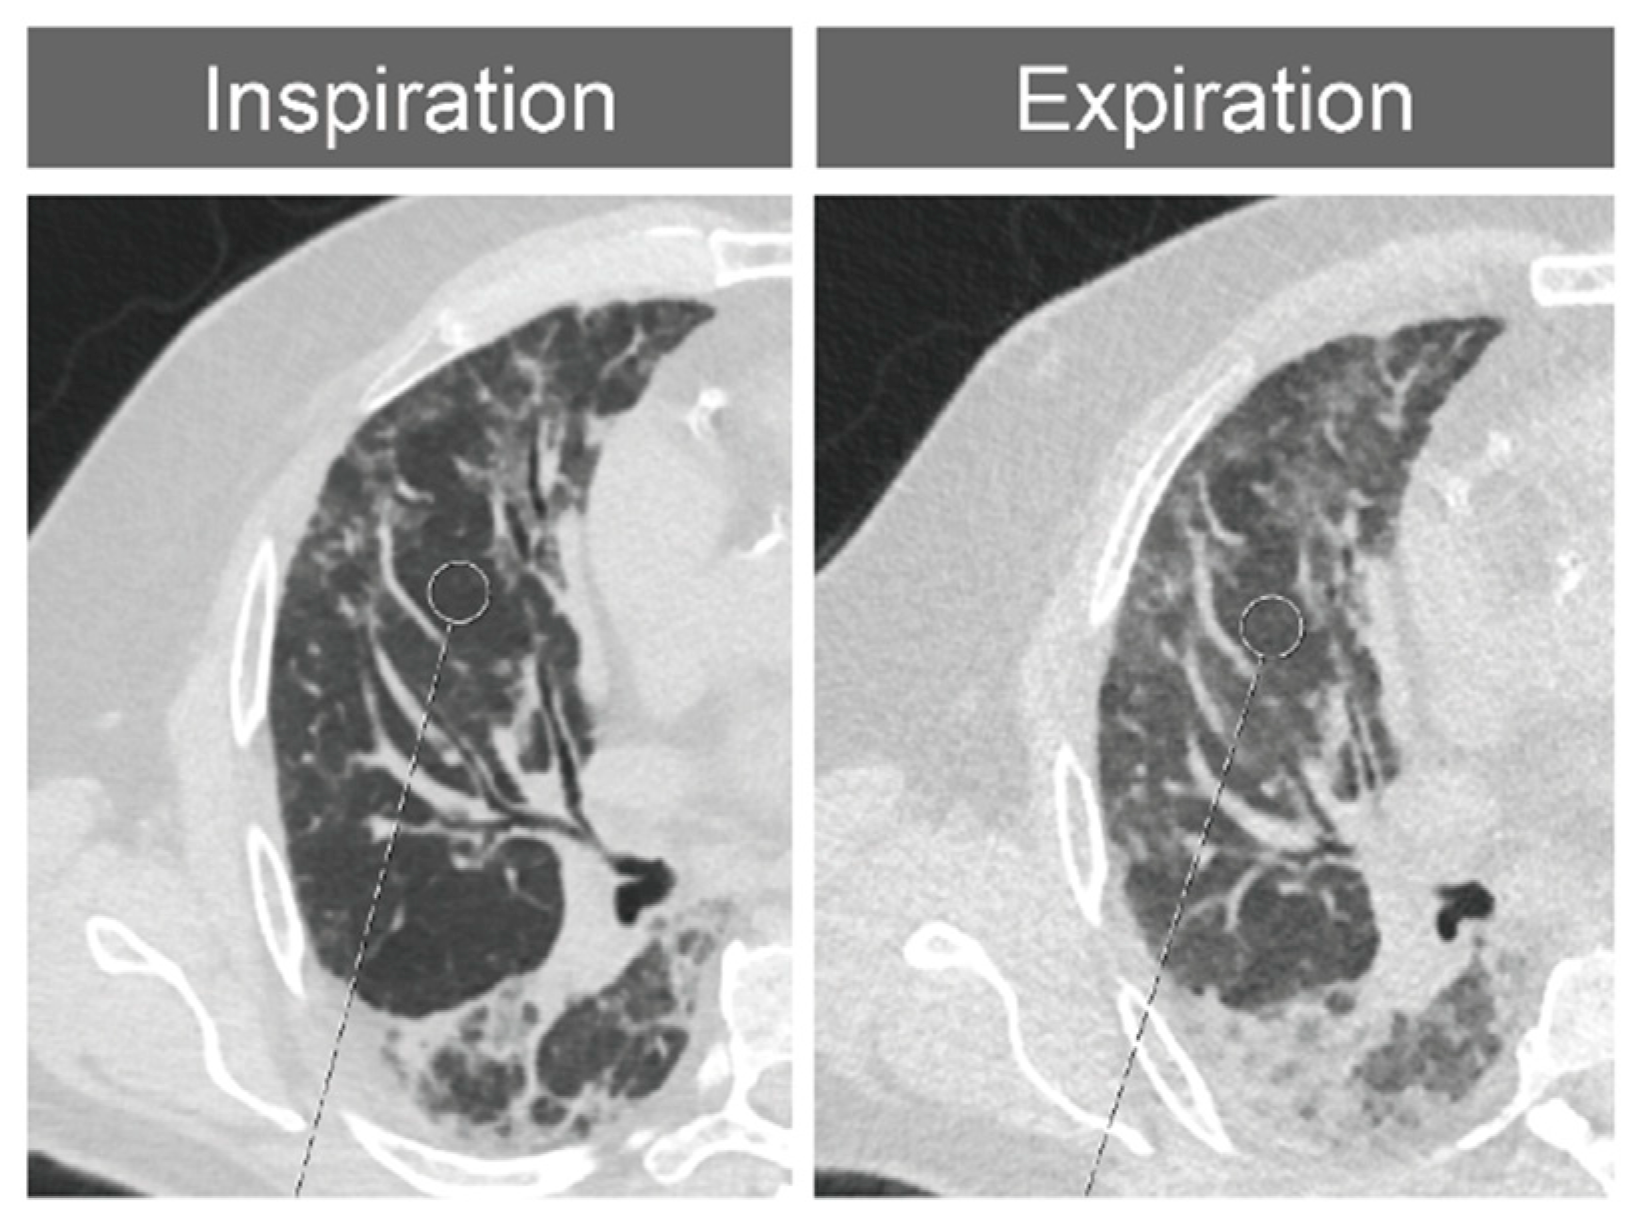

Density measurements were performed in each bronchopulmonary segment of both lungs according to the anatomical division of the lung in inspiration and expiration. For symmetry, two regions of interest (ROIs) each were measured in the apicoposterior segment (B1/2) and in the anteromedial segment (B7/8), giving a total of 40 measurements per patient and 4800 measurements for all patients and both readers in total. The measurements were performed independently by a radiologist with 5 years of experience in the assessment of CT imaging of the lungs (K.S.Y.) and a reader in continued education (W.M.F.) under the supervision of an experienced radiologist with 18 years of experience (P.A.). In radiologically healthy-appearing lung tissue, regions of interest with a diameter of 15 mm were manually annotated in axial slice images of 1 mm thickness in the lung window (window center: −500 Hounsfield units [HU]); window width, 1500 HU). When measuring the density in IPF, HP or SSc patients, special care was taken to place the ROI only in non-pathological-appearing lung tissue (Figure 1). Lung areas showing radiographic signs of fibrosis, emphysema, air trapping or other pathologies were avoided. If possible, pulmonary vessels were not included in the ROI. No measurement was performed in lung segments that were so altered by the underlying disease that normal-appearing lung parenchyma could no longer be identified.

Figure 1.

Placement of an ROI in healthy-appearing lung tissue of a patient with IPF while avoiding the pulmonary vessels.